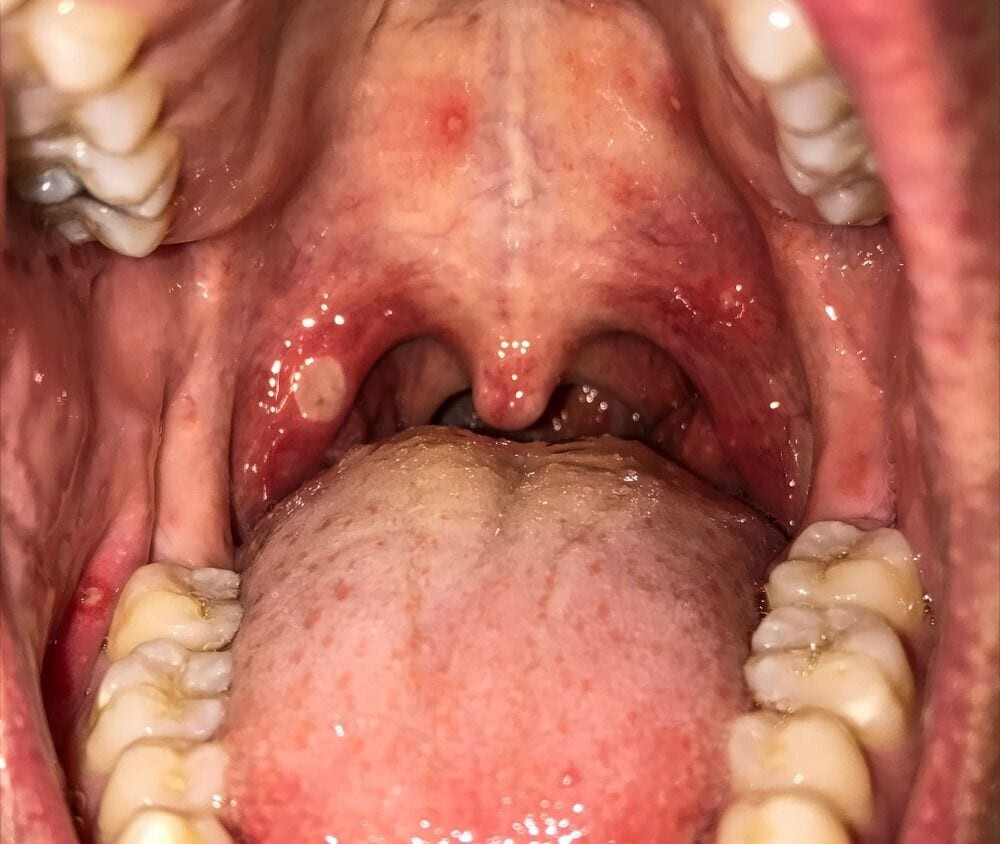

Four Possible Causes of Roof of Mouth Pain & Their Treatments

Why is the Roof of my Mouth Sore?

If the roof of your mouth (palate) is sore, it can make eating and drinking uncomfortable and difficult. You may also have problems speaking normally.

Several things can cause a sore palate, including very hot coffee, infections, allergies, and injuries. In most cases, it's not a serious condition and typically goes away by itself. However, if the pain is severe or lasts more than a few days, contact a medical professional.

4 Possible Causes of Roof of Mouth Pain

Here are four potential causes of palate pain: